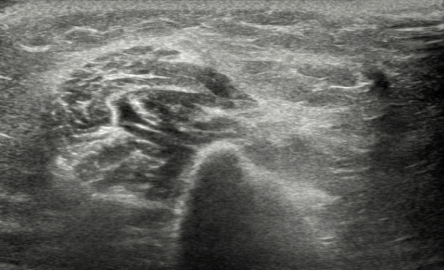

수술 후

2022.09.20